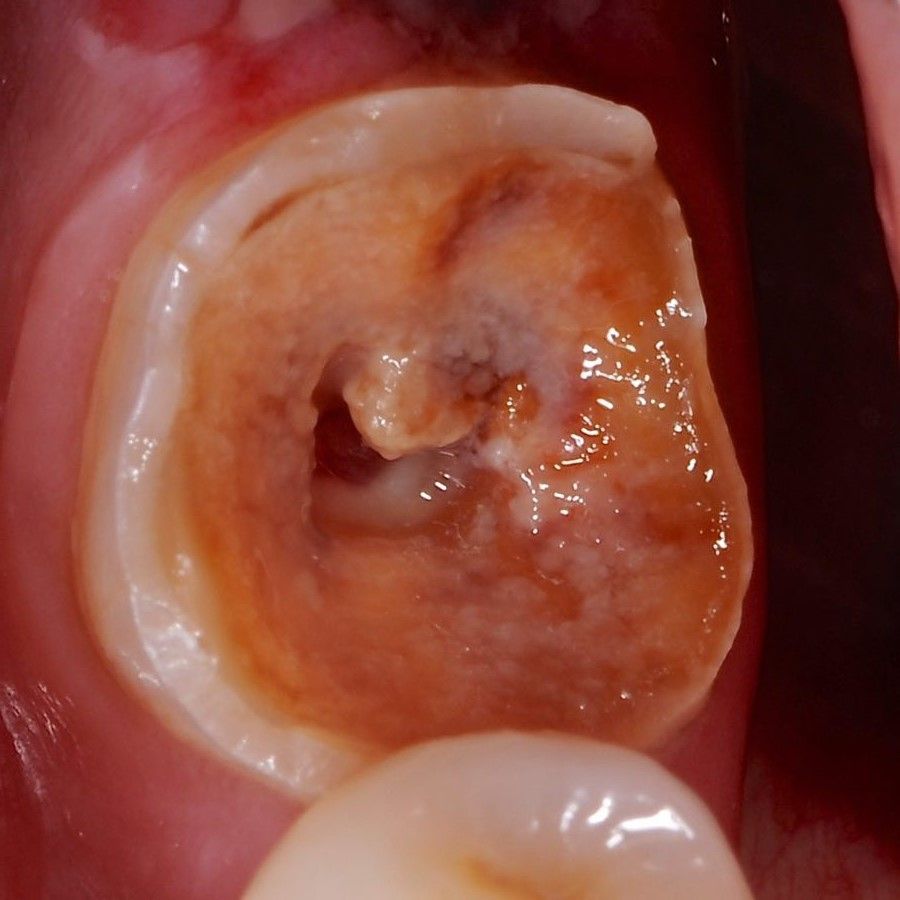

Back Teeth Repair of Grinding Fractures